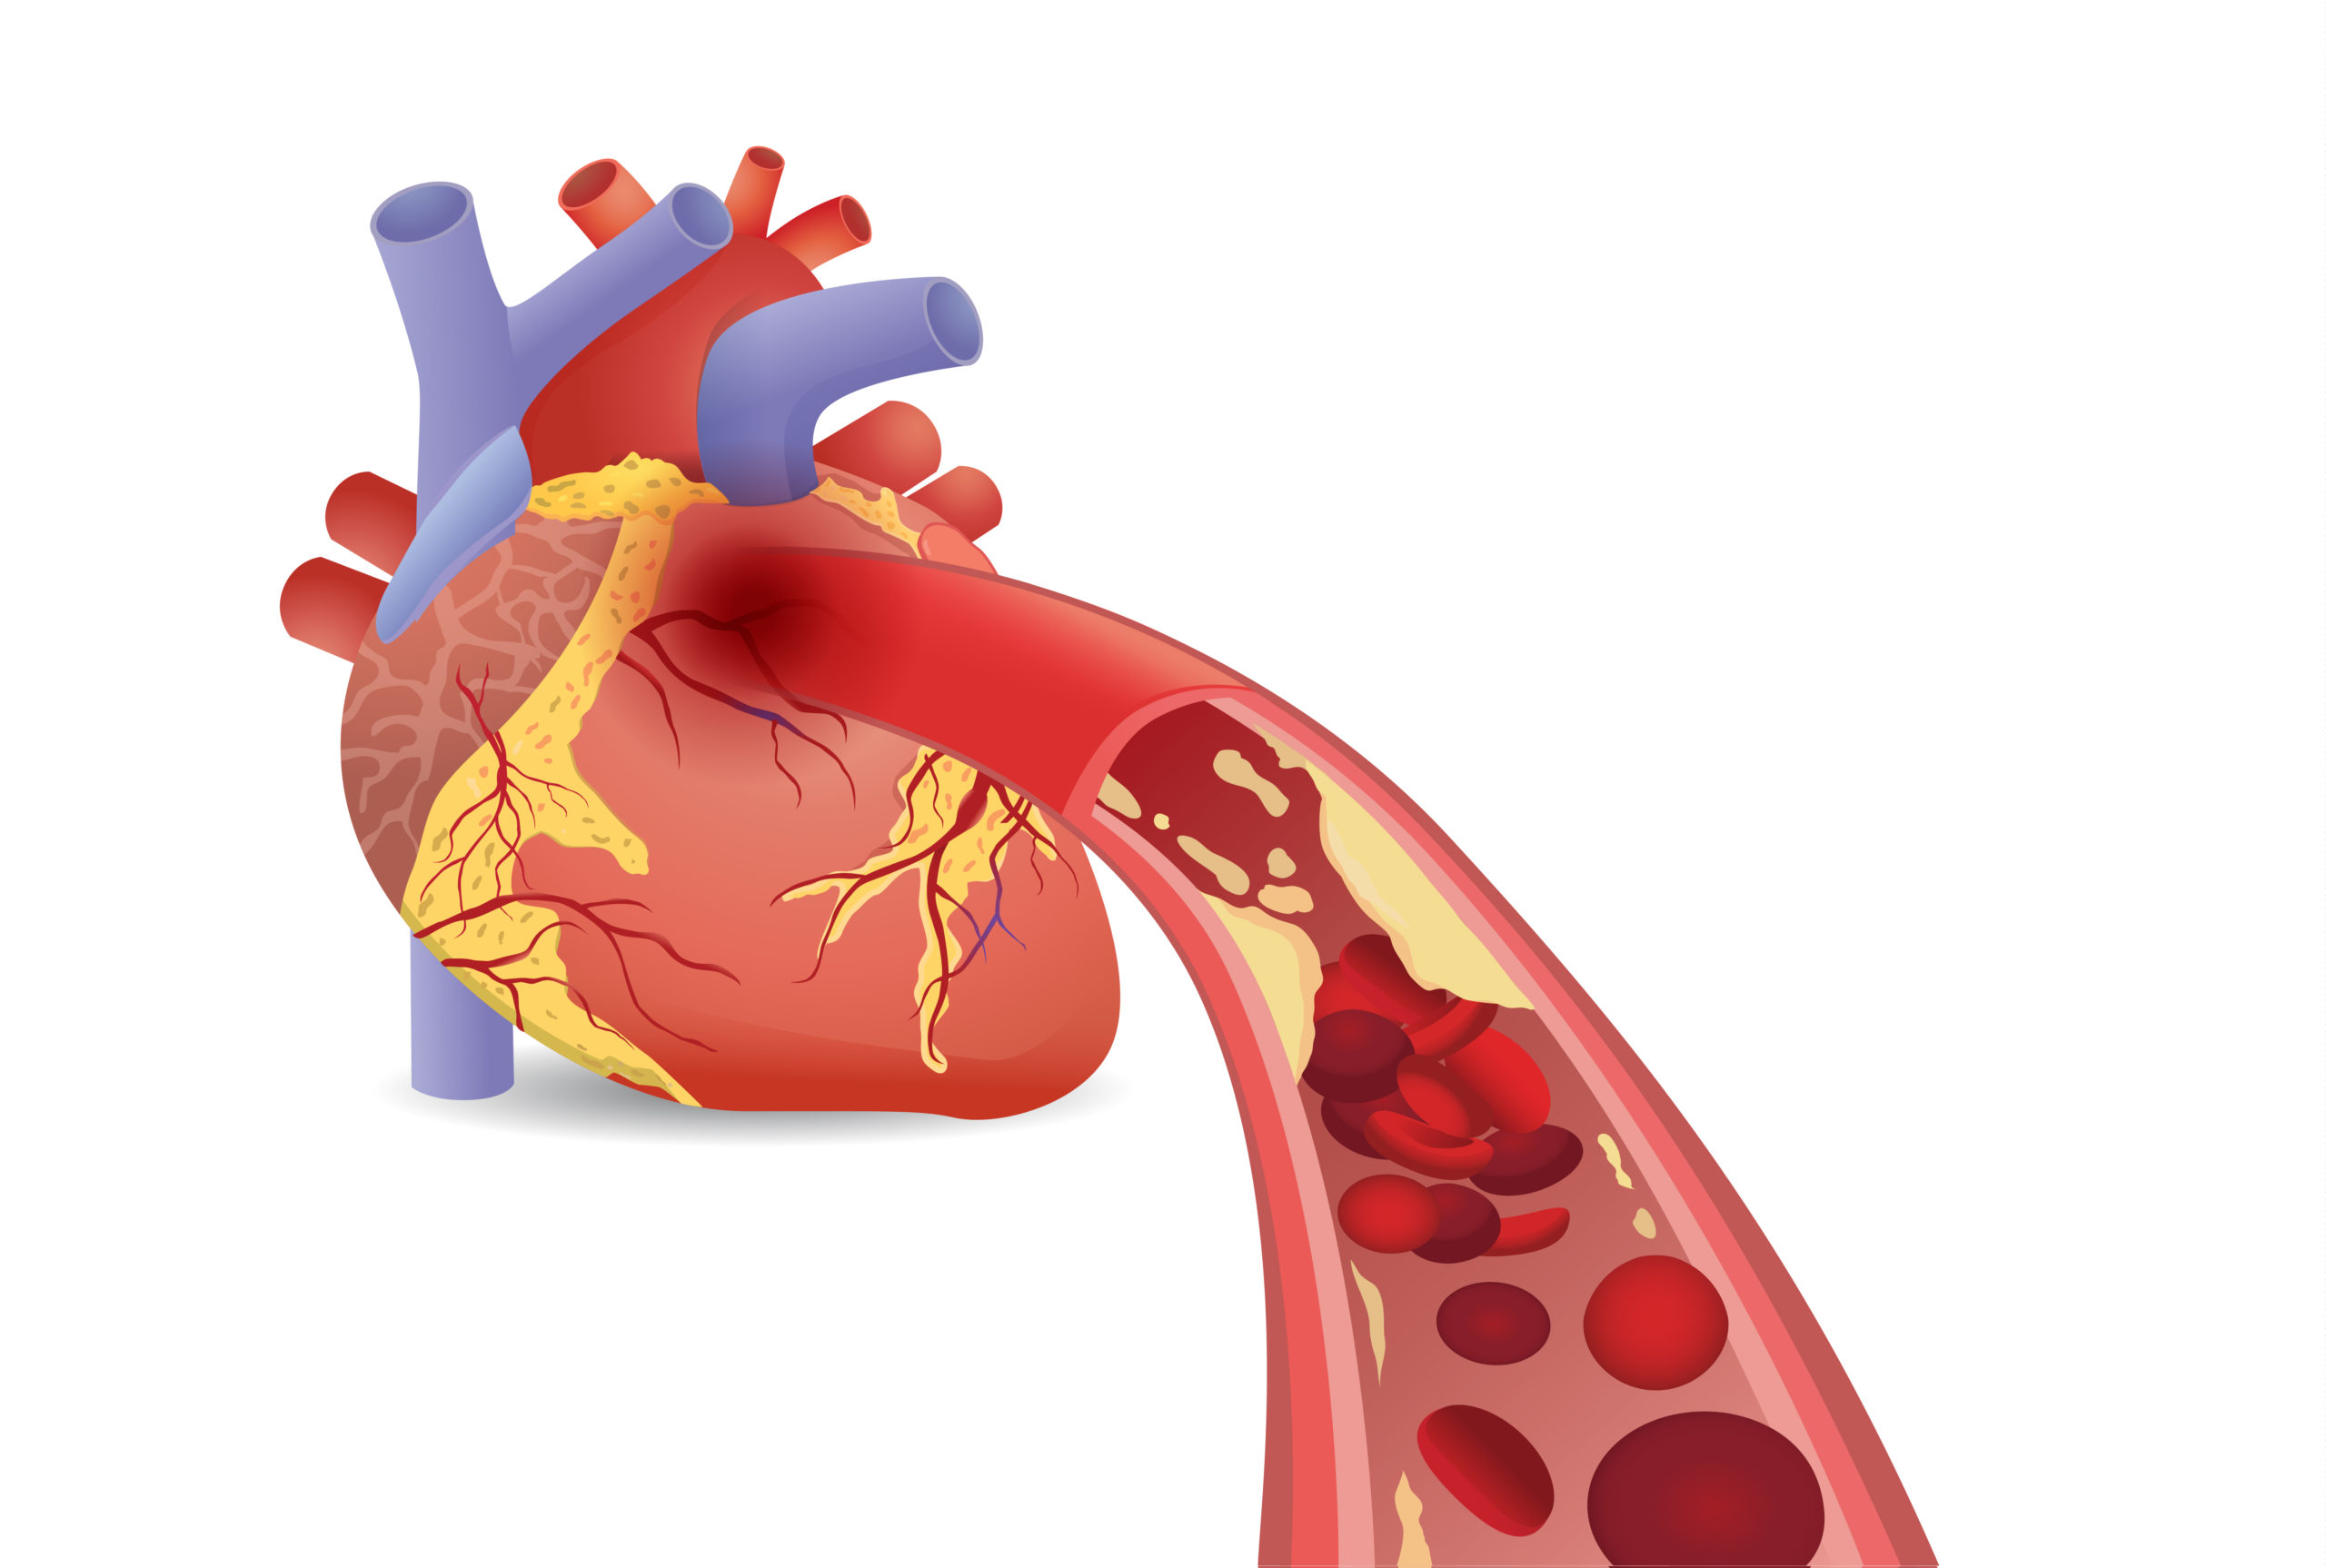

stent

In the BASKET-SMALL 2 randomized controlled trial, researchers compared the effect of a drug-coated balloon (DCB) ...

Deep learning may be able to predict incomplete stent expansion, new research in JACC: Cardiovascular Interventions ...

Deep learning may be able to predict incomplete stent expansion, new research in JACC: Cardiovascular Interventions ...

A novel NanoCoated Coronary Stent (NCS) failed to meet noninferiority criteria to a drug eluting stent, new trial ...

Discontinuation of aspirin at 90 days following stenting and continuing on P2Y12 inhibitor monotherapy, was not ...

The Absorb bioresorbable vascular scaffold was shown to be noninferior to the Xience Cobalt ...

A novel polymer-free amphilimus-eluting stent was found to be safe and efficacious compared to the latest-generation ...

A polymer-coated zotarolimus-eluting stent (Resolute Onyx) with a novel thin-strut metallic platform demonstrated ...

Ultra-thin strut drug-eluting stents (DES) may promote better clinical outcomes than thicker strut second-generation DES ...